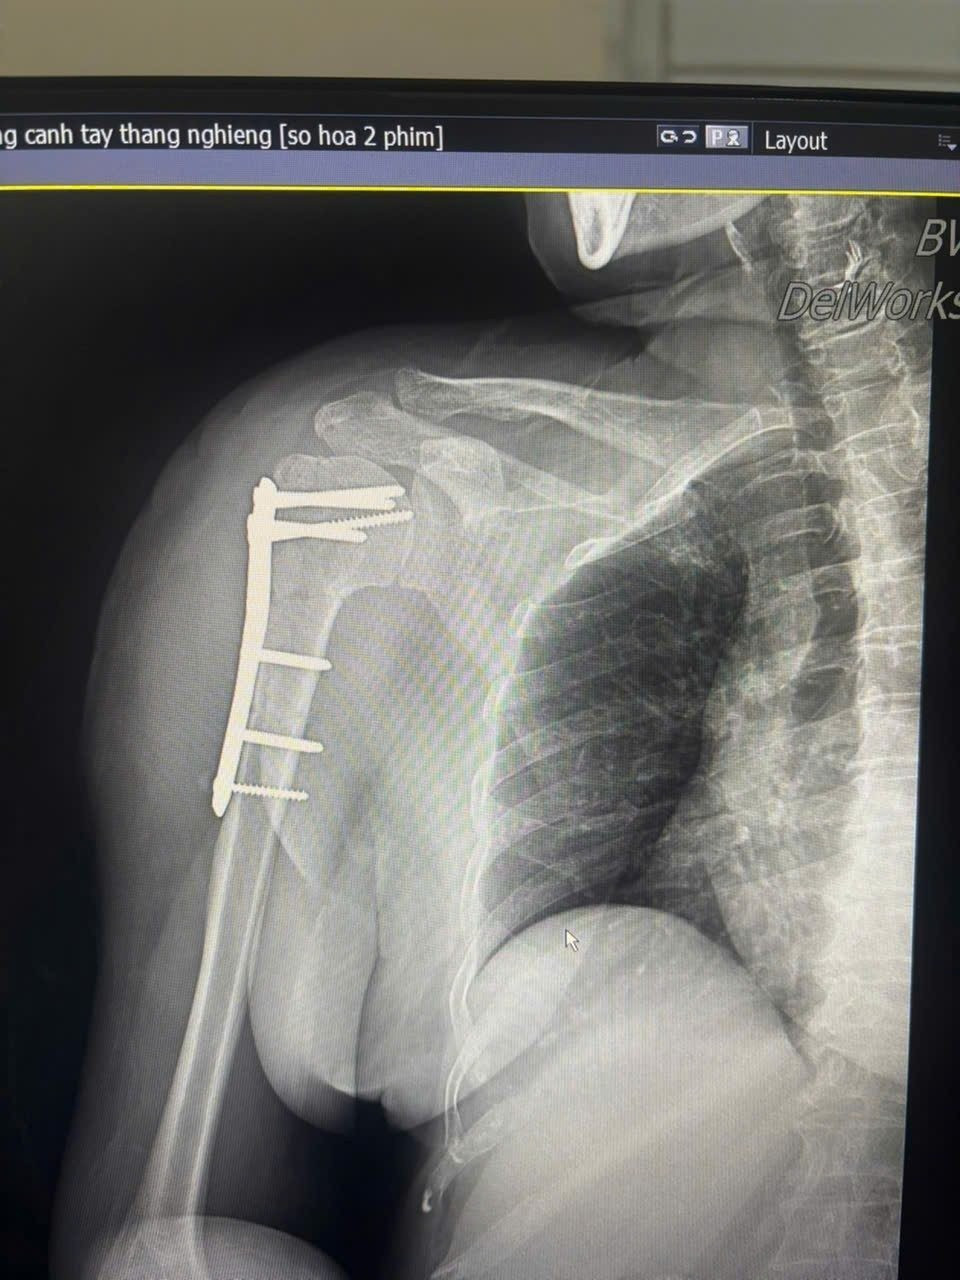

xuong-canh-tay.jpg

Hình ảnh gãy xương cánh tay trên phim chụp - Ảnh BVCC

Trước đó, bệnh nhân bị ngã được đưa vào viện trong tình trạng đau nhiều vùng vai phải, hạn chế vận động. Qua thăm khám lâm sàng và chẩn đoán hình ảnh, người bệnh được xác định gãy kín đầu trên xương cánh tay phải và được chỉ định phẫu thuật kết hợp xương bằng nẹp vít khóa.

Ca phẫu thuật do BSCKII. Đỗ Văn Cường trực tiếp thực hiện – một kỹ thuật hiện đại, mang lại hiệu quả cao, đặc biệt phù hợp với người cao tuổi và bệnh nhân có loãng xương.